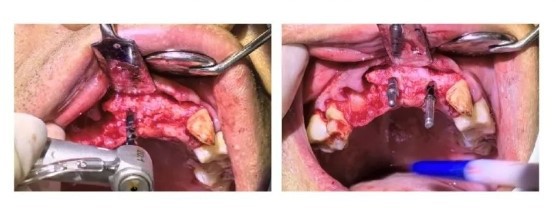

Extraction of the affected tooth and upon flap elevation, extensive bone deficiency is observed in the mesial aspect of A4 and the distal aspect of A2.

Thorough removal of granulation tissue and positioning with a round bur.

A1B2 pilot drill positioning, and verification of axial alignment with a parallel pin.

Using a drill guide and parallel pin, gradually expanding the hole while verifying implant depth and alignment for parallelism.

Sequential implantation of three Manners Apex dental implants.

Preparation of nourishing holes and soft tissue debridement.

Performing Guided Bone Regeneration (GBR) with the implantation of Osseograft bone powder and a bone membrane.

Aligning and suturing the gingiva and shaping the gingival papilla with nylon thread.